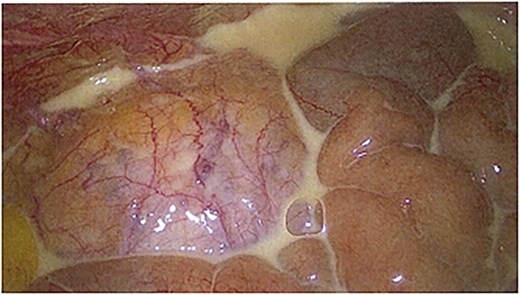

On day 4 of admission, she progressed to theatre for a laparoscopic cholecystectomy. On entry to the abdominal cavity, milky/purulent fluid appeared in all four quadrants (Fig. 1). A diagnostic laparoscopy was performed to try to identify the cause of this. Her pelvic organs, caecum, transverse, and sigmoid colon were unremarkable. The small bowel was examined in its entirety, revealing no abnormality. The stomach and duodenum were inspected and were normal. There was saponification of the fat overlying the pancreas, and adhesions were present from the liver to the abdominal wall. The gallbladder was thin-walled (Fig. 2). No alternative source of peritonitis was identified; therefore, the decision was made to proceed with the cholecystectomy, which was uncomplicated. A 15 French Blake drain was placed in the pelvis.

Laparoscopic image showing a thin-walled gallbladder prior to cholecystectomy.